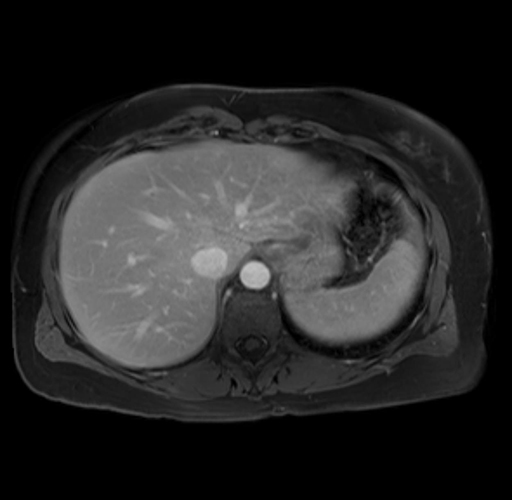

Imaging Analysis

Look through the patient's CT scan to identify any areas of concern for the necessary procedure.

Based on your CT findings, which issue(s) are present and would give reason for "planned slowing down moment(s)" in this case?